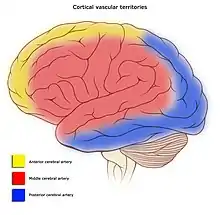

Blood supply and drainage

Blood supply to the cerebral cortex is part of the cerebral circulation. Cerebral arteries supply the blood that perfuses the cerebrum. This arterial blood carries oxygen, glucose, and other nutrients to the cortex. Cerebral veins drain the deoxygenated blood, and metabolic wastes including carbon dioxide, back to the heart.

The main arteries supplying the cortex are the anterior cerebral artery, the middle cerebral artery, and the posterior cerebral artery. The anterior cerebral artery supplies the anterior portions of the brain, including most of the frontal lobe. The middle cerebral artery supplies the parietal lobes, temporal lobes, and parts of the occipital lobes. The middle cerebral artery splits into two branches to supply the left and right hemisphere, where they branch further. The posterior cerebral artery supplies the occipital lobes.

The circle of Willis is the main blood system that deals with blood supply in the cerebrum and cerebral cortex.